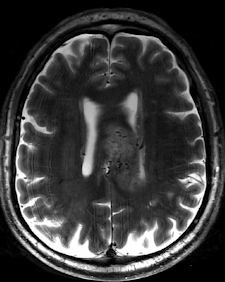

| Two 7-tesla images of a glioblastoma patient. Left: T2-weighted image shows brain lesion with very high spatial resolution. The heterogeneity in the lesion is already visible. Right: Time-of-flight MR angiogram shows the arterial vessels at the periphery of the lesion. The irregular vessel structure indicates neoangiogenesis, and it would be very interesting to see whether this vascular structure changes under new forms of neoangiogenic therapy. Image courtesy of Dr. Michael Bock. |

"High-resolution MRI in the brain, and in other anatomical areas (e.g., the knee), will become the first established clinical applications of high-field MRI," he said. "For example, we are able to visualize the tiny neovasculature in brain tumors, so high-field MRI might be a powerful tool to assess therapy response to the more and more popular neoangiogenic treatment," he commented.

Operating at increased magnetic fields makes it easier to obtain T2* contrast-enhanced images and improved implementation of susceptibility-weighted imaging, in which the phase of gradient-echo images provides information about local variation of magnetic susceptibility, according to Richard Bowtell, a professor from the Magnetic Resonance Centre, School of Physics and Astronomy, at the University of Nottingham in the U.K. In the brain, such variation appears to be dominated by differences in iron concentration and myelin content, so that high-field SWI may provide useful information about the progression of neurodegenerative disease. The elevated T1 relaxation times at 7-tesla also offer benefits for arterial spin labeling and time-of-flight angiography.